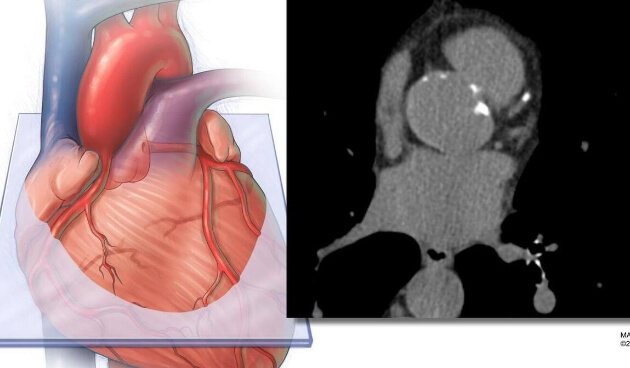

El estudio realizó un seguimiento de casi 12.000 adultos durante aproximadamente 16 años. Los investigadores aplicaron IA a las tomografías estándar de calcio en arterias coronarias de los participantes para medir la grasa que rodea el corazón. Compararon el valor predictivo de esta medición, tanto de forma independiente como en combinación, con dos enfoques estándar de evaluación del riesgo: la ecuación PREVENT de la American Heart Association, que incorpora factores tradicionales como edad, sexo, presión arterial, colesterol, diabetes y otras variables, y la puntuación de calcio en arterias coronarias, que cuantifica la placa calcificada en las arterias coronarias.

La cuantificación del calcio en arterias coronarias se utiliza ampliamente para evaluar el riesgo cardiovascular. Este estudio demuestra que puede extraerse información adicional de la misma exploración sin necesidad de pruebas adicionales ni costes añadidos.